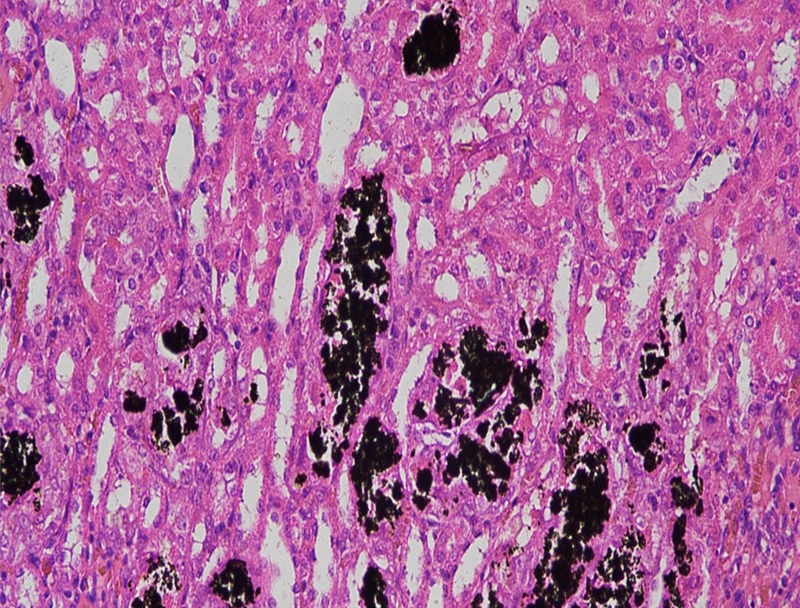

HE染色实验(病理常规染色)

(一)实验目的通过苏木素(碱性染料)和伊红(酸性染料)对组织切片进行染色,使细胞核、细胞质呈现不同颜色,清晰显示组织细胞的形态结构、排列方式,为病理诊断提供基础依据。(二)实验材料1. 样本:已烤好的病理石蜡切片;2. 试剂:苏木素染液、伊红染液、1%盐酸酒精分化液、自来水(返蓝用)、梯度酒精(...